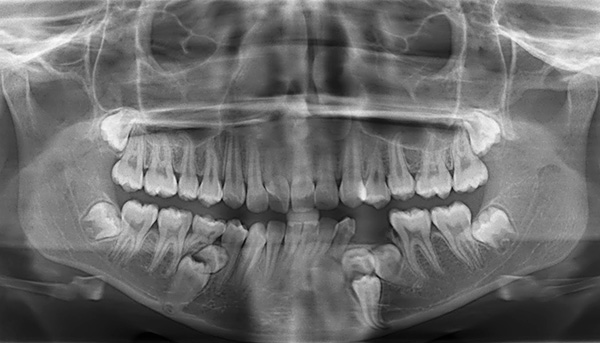

Dos métodos diagnósticos adicionais, os exames radiológicos são obrigatórios:

- Ortopantomograma (em crianças com mais de 5 anos). Permite avaliar a assimetria das estruturas ósseas dos maxilares;